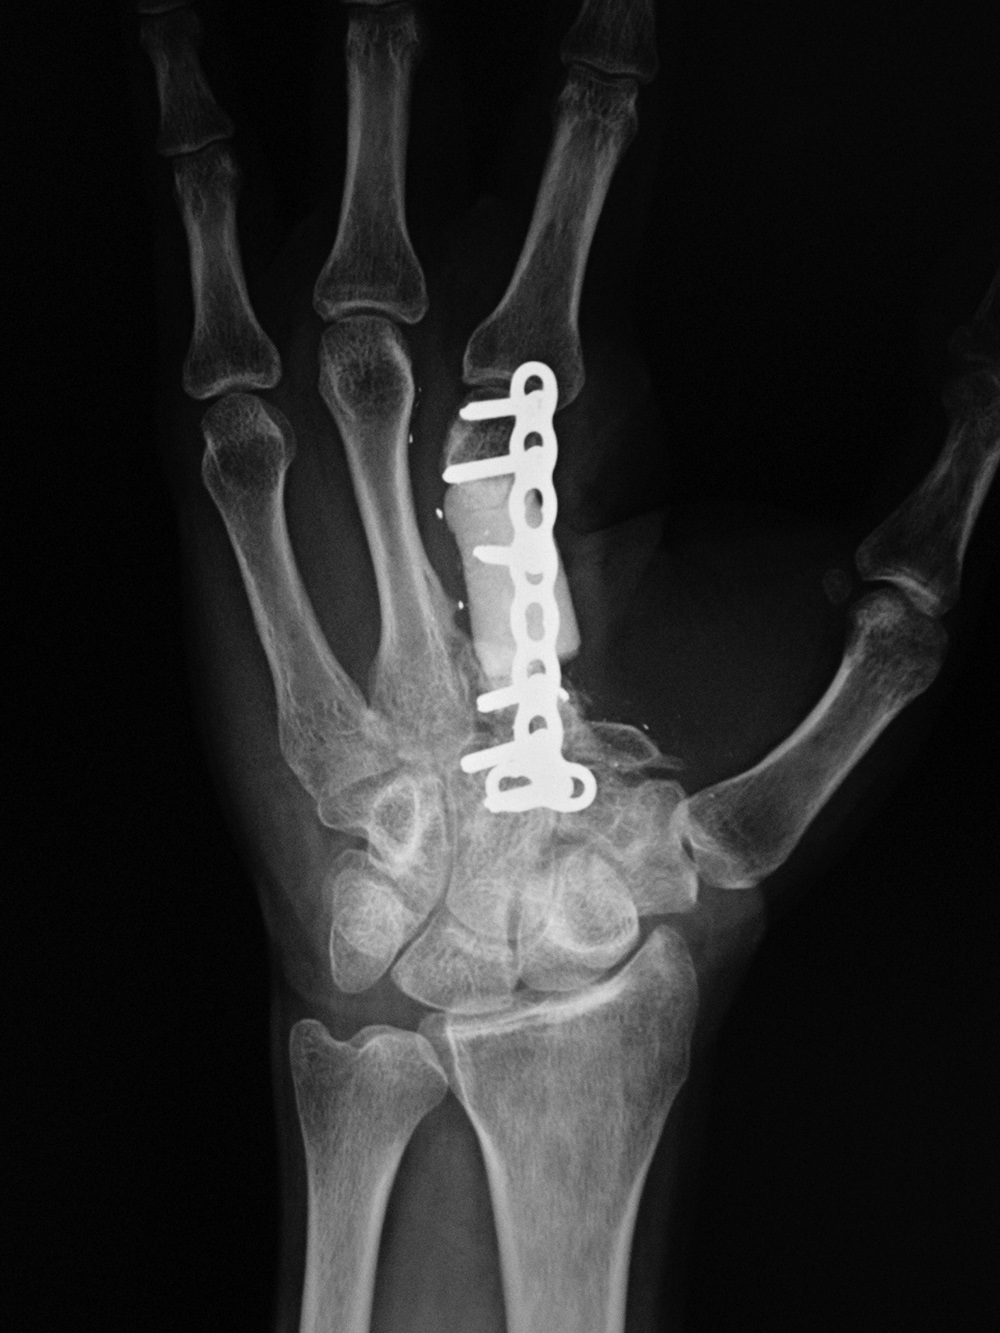

36 year-old man with loss of index finger and a portion of the third metacarpal from a gunshot wound. The antibiotic laden cement block is stabilized by a small malleable plate and screws for treatment of third metacarpal bone infection.